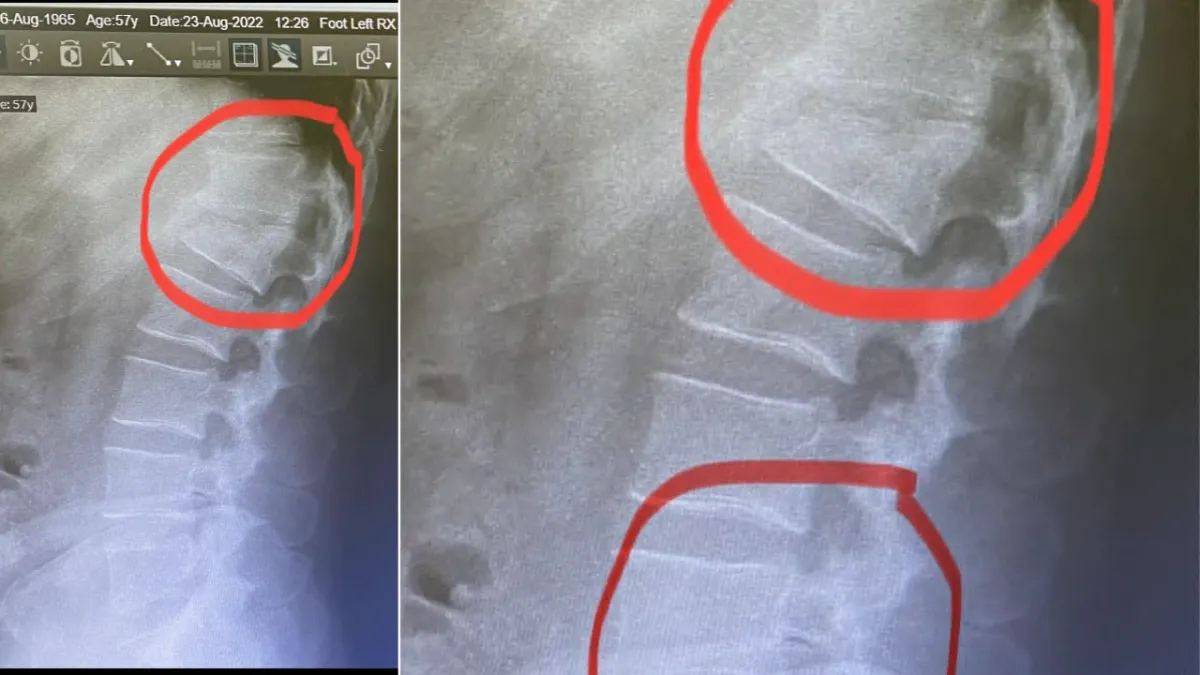

Számtalan sérülésem volt, a legsúlyosabb a gerincsérülésem

Zsolt a kórházban életveszélyes állapotban volt, egyszer újra is kellett éleszteni. A sérülései súlyosak voltak: a gerincéből vér szivárgott a hasüregbe, ami az életfunkcióit veszélyeztette.

– Három hónapig ágyban feküdtem, és újra kellett tanulnom járni. Most már azt mondom, szerencsésen megúsztam műtét nélkül, de a fájdalmak valószínűleg életem végéig elkísérnek majd – tette hozzá.